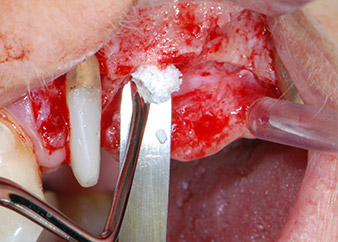

Prima del posizionamento dell'impianto, e in seguito a verifica dell'integrità della membrana schneideriana (Fig. 9), il seno mascellare interno è stato rialzato in corrispondenza di entrambi i siti di impianto mediante materiale xenogenico di sostituzione ossea (Bio-Oss, Geistlich Biomaterials) (Fig. 10).

Gli impianti (Restore, Keystone Dental,, diametro 3,75 mm, lunghezza 8,0 mm) sono stati posizionati con il motore per impianto (Figg. 11 e 12).

Le mancanze di tessuto osseo attorno gli impianti, in corrispondenza dell'aspetto mesiale del dente 27 e attorno alla radice buccale del dente 24, sono stati riempiti con particelle xenogeniche di sostituzione ossea e coperte con una membrana di collagene assorbibile (Bio-Gide, Geistlich Biomaterials) per tecnica di innesto GBR (Figg. 13 e 14).